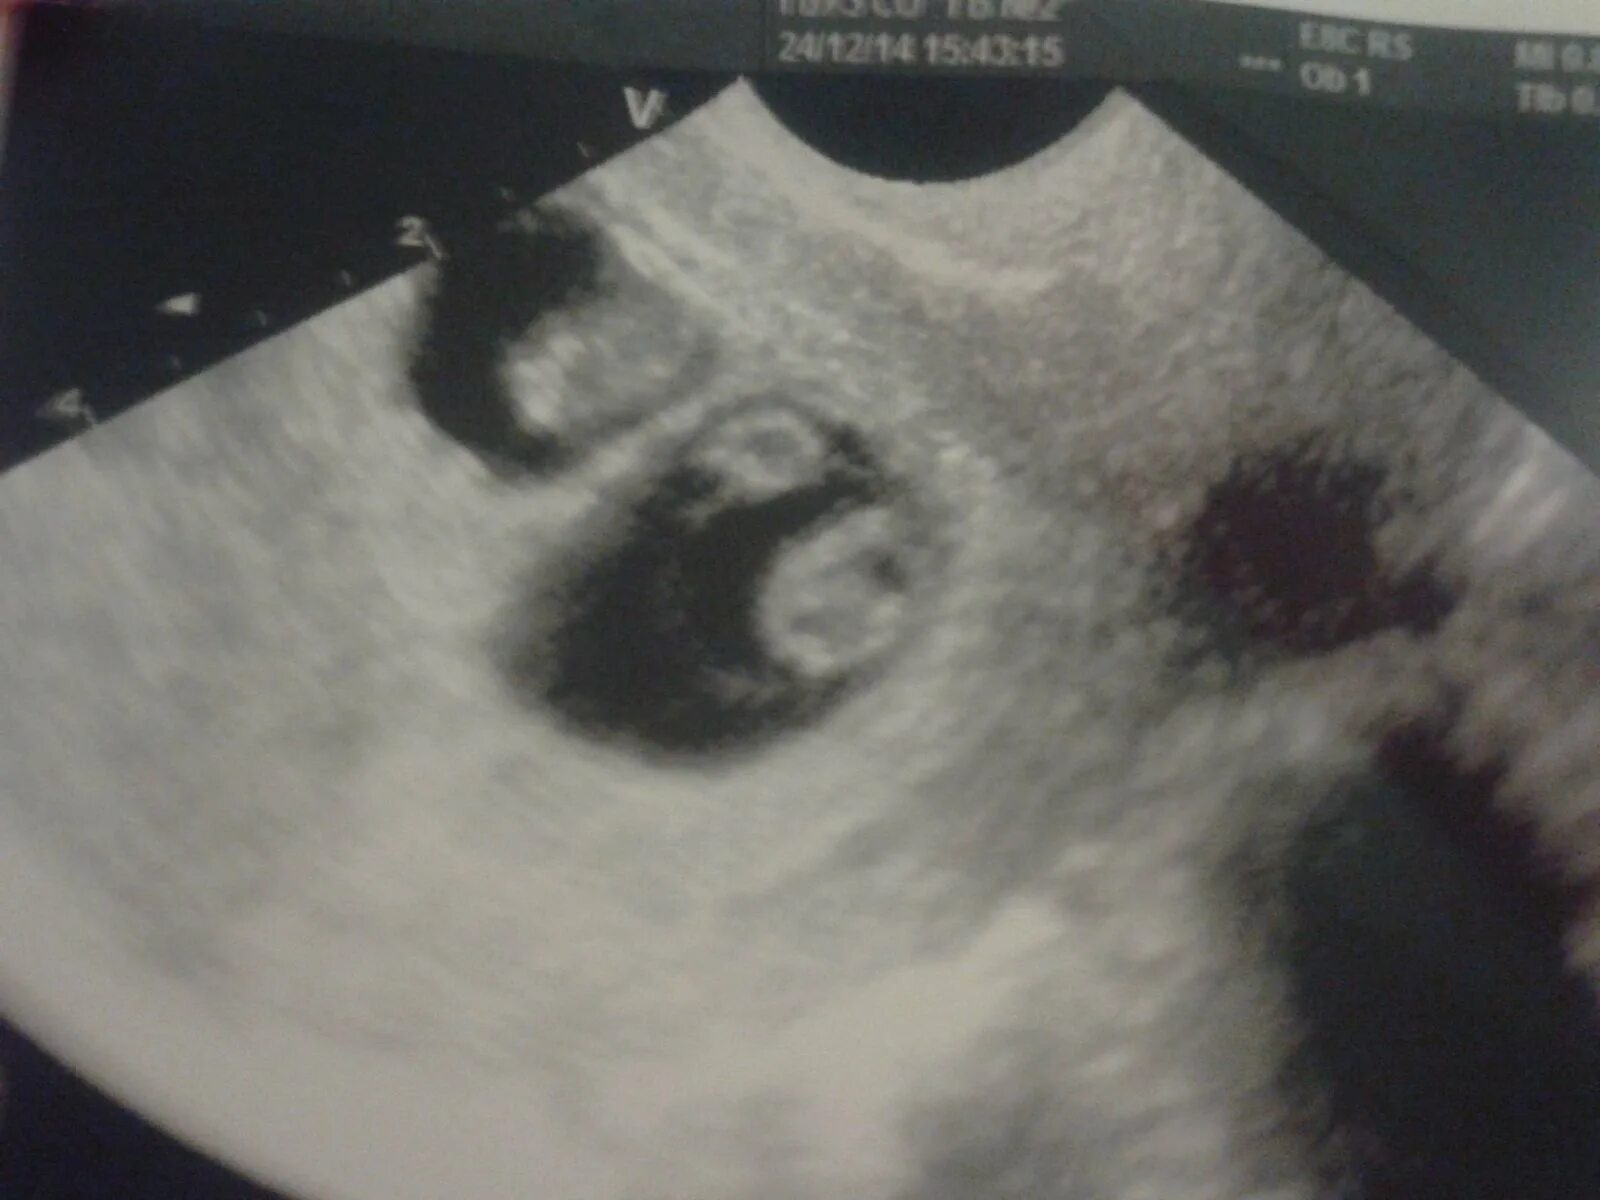

На каком сроке можно увидеть двойню